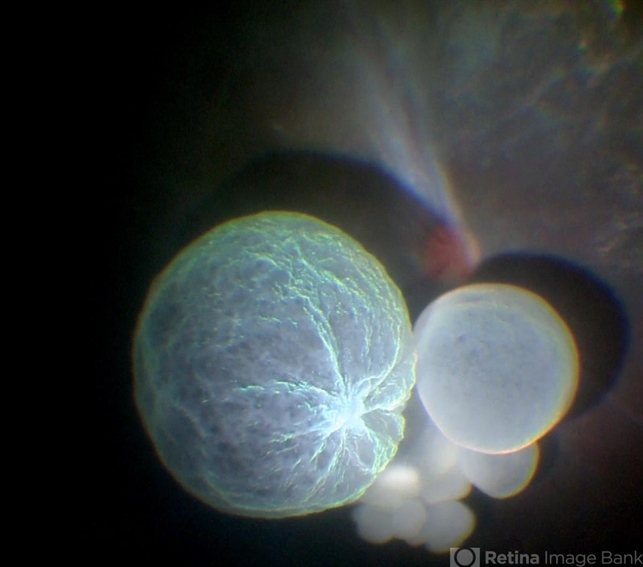

- cysticercosis, scolex

- Intraoperative fundus picture of right eye of a 18-year-old boy with complaints of DOV for the past 2 months. There were 12 intravitreal cysts in total with vitritis sclerosis retinal vessels and TRD. To note here, the largest cyst has a flimsy wall and no scolex (possibly ruptured) and the rest of the smaller cysts have a scolex and a taut wall.